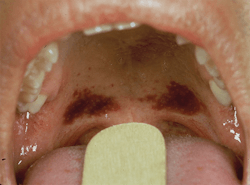

In addition to your clinical diagnosis or differential diagnosis, some additional documentation is recommended here. Take photos (intra- and extraoral) using a ruler or scale next to injuries to show size. Even a cotton roll or periodontal probe can be used, because it is a size that is reproducible and consistent. Coins have been used in some cases for a size reference because that was all that was on hand, and it works! Include quoted remarks, comments, explanations made by the child and by the parent/guardian/caretaker, and take very descriptive notes on hard-and-soft tissue findings and any comments on the observable demeanor of the child and adult. Remember that this might be the only chance to document an injury before it heals.